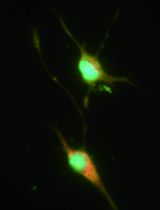

Dendritic cells (DC) are antigen-presenting cells, which play a critical role in the regulation of the adaptive immune response. They act as a bridge between the innate and the adaptive immune systems. An approach to study their function and potentiality is to generate DC-like cells by culturing CD14+ monocyte-enriched peripheral blood mononuclear cells (PBMC). In the presence of GM-CSF and IL-4, these cultures give rise to large numbers of DC-like cells. Generating human-DC from PBMC is a useful tool to study biological functions of human DC.